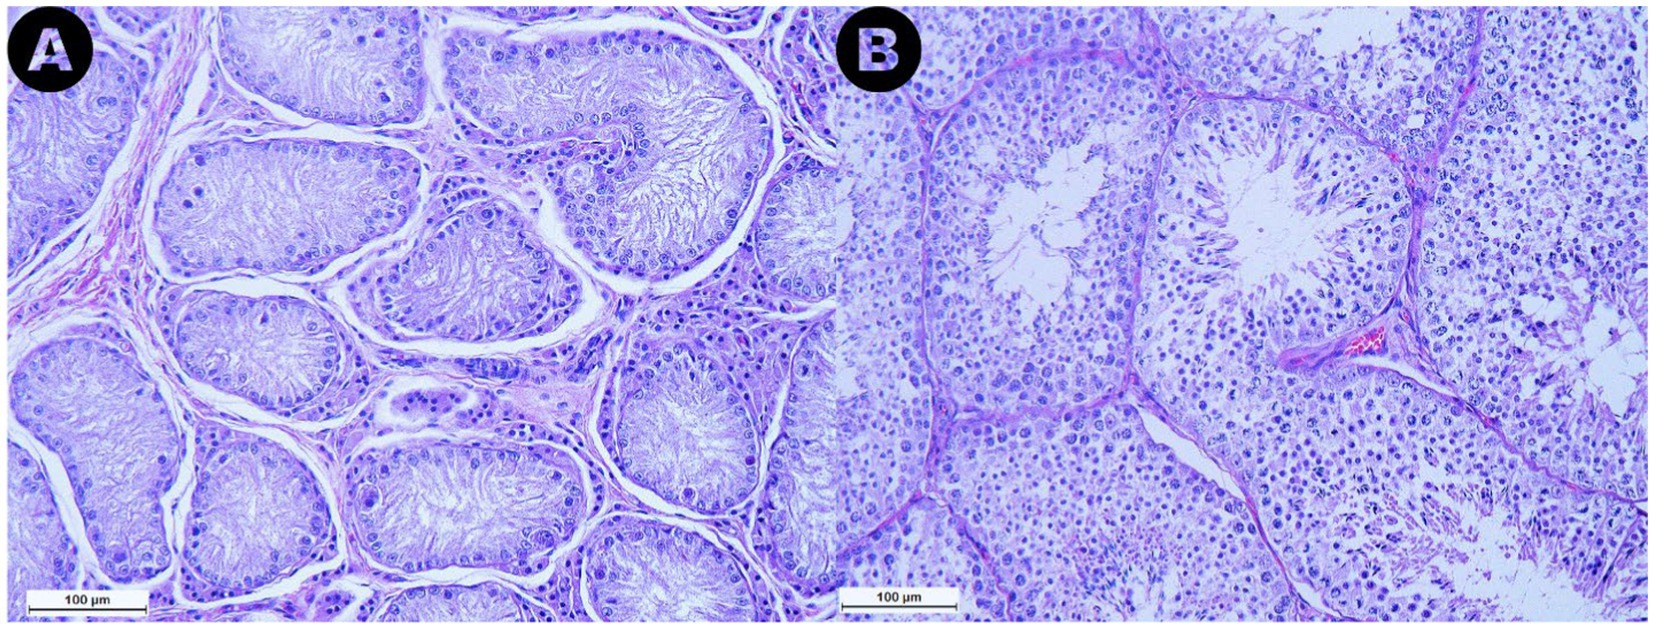

3.2.1 Histología general

Las muestras analizadas de la categoría RET exhibieron túbulos seminíferos con pocas células germinales, con el 76,7% de las secciones de túbulos evaluadas clasificadas como túbulos solo de células de Sertoli. Además, se observó una marcada reducción o ausencia de la luz (Figura 4A). Además, se evidenció la degeneración seminífero de los túbulos, caracterizada por una pérdida general de los detalles celulares. La membrana basal que rodea los túbulos parecía engrosada en comparación con las muestras de los grupos CONTRA y DES. Además, en el espacio intersticial de los testículos RET, se observó subjetivamente un aumento en el número de células de Leydig, acompañado de una mayor cantidad de tejido conectivo (Figura 4A), en comparación con las muestras de DES (Figura 4B).